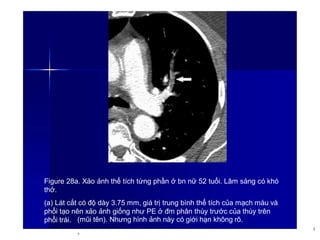

Figure 28a. Xảo ảnh thể tích từng phần ở bn nữ 52 tuổi. Lâm sàng có khó

thở.

(a) Lát cắt có độ dày 3.75 mm, giá trị trung bình thể tích của mạch máu và

phổi tạo nên xảo ảnh giống như PE ở đm phân thùy trước của thùy trên

phổi trái. (mũi tên). Nhưng hình ảnh này có giới hạn không rõ.